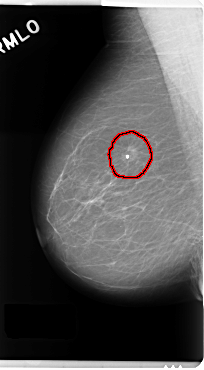

C_0190_1.RIGHT_MLO

RIGHT_MLO LINES 4800 PIXELS_PER_LINE 2648 BITS_PER_PIXEL 12 RESOLUTION 50 OVERLAY

FILE: C_0190_1.RIGHT_MLO.OVERLAY

TOTAL_ABNORMALITIES 1

ABNORMALITY 1

LESION_TYPE CALCIFICATION TYPE ROUND_AND_REGULAR DISTRIBUTION CLUSTERED

LESION_TYPE MASS SHAPE OVAL MARGINS SPICULATED

ASSESSMENT 5

SUBTLETY 5

PATHOLOGY MALIGNANT

TOTAL_OUTLINES 1

BOUNDARY